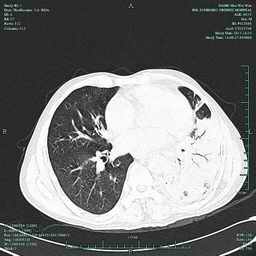

图片1 CT可见左下肺大片实变

鄞州人民医院呼吸科副主任医师徐涛说:“近9年来,老华经常会莫名咯血,象《红楼梦》中的林妹妹那样,经常会捂着手绢咳嗽,手绢上留下点点血丝。10月下旬,因为有个亲戚在宁波打工,老华从金华来到宁波,顺便请宁波医生检查 下是什么原因引起咯血。10月26日,鄞州人民医院为老华检查后发现,老华左肺部有大面积的炎症。为了确定是什么原因导致的,决定10月31日给他作气管镜检查,以确诊出血原因。检查时,结果发现他气管里有好几个突起的球形状。按照常规,气管镜检查后要对可疑处采样活检。意想不到是,经对老华气管突起的球形状部位采样后,老华突然出血,大口大口从口腔和鼻腔喷出鲜血,近2000ml,引起失血性休克。为防止患者因气道堵塞危及生命,闻讯赶来的呼吸科博士、副院长俞万钧立即组织现场抢救。医生对患者实施现场急救,并紧急请求麻醉科、ICU、介入科等专家前来抢救。近2个小时中,患者经麻醉科专家实施双腔气管插管并进行支气管镜镜下治疗、介入科专家在DSA下对其气管内破损的血管实施介入止血手术以及输入鲜血1600毫升、血浆1200毫升及大量液体后,终于把老华拖离了鬼门关。